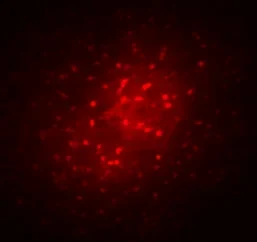

Das Bild entstand,

indem in einem Hirnschnitt ein Astrozyt mit einem Marker (Biozytin, rot) gefüllt wurde. Dieses Molekül diffundiert bei intakter Kopplung in benachbarte Astrozyten, so dass ein ganzes funktionelles Netzwerk sichtbar wird.